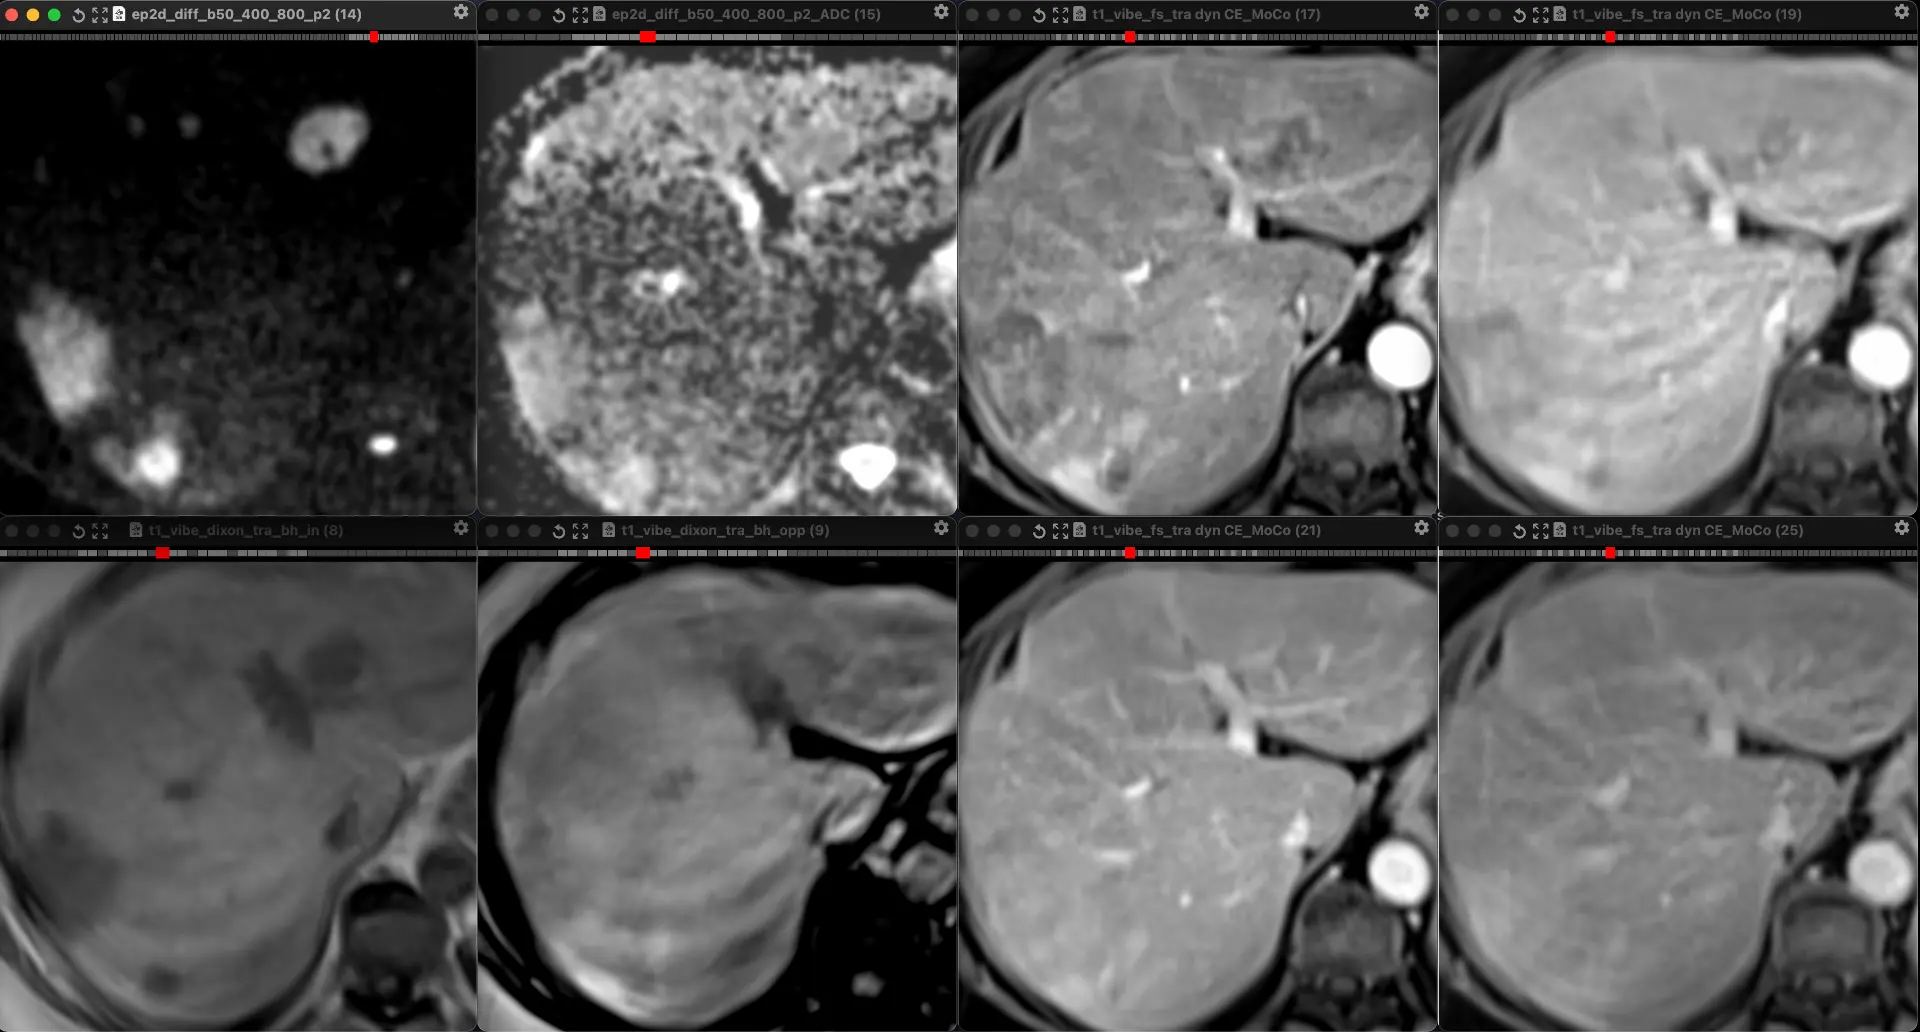

ЖЕНЩИНА 38 лет, фокальное изменение печени выявлено на УЗИ.

Повторные #КТ (с разницей в 2,5 месяца) без динамики. Имеется медленное, постепенное, слабоинтенсивное накопление контраста от периферии к центру.

На #МРТ - очень высокий сигнал на Т2, низкий на Т1, «лучистые» контуры. Истинное ограничение диффузии (ADC=460±109х10-6 кв.мм/с). Накопление контраста такое же, но на МРТ лучше видны краевое узелков накопление в артериальную фазу, тотального контрастирования нет даже на отсроченной фазе (через 5 минут).

Картина характерна: это гиалинизированная/ #склерозированнаягемангиома. Характерное стяжение контура является свидетельством склерозирования: уменьшения объёма, «рубцевания».

Гемангиомы с суженными кавернозными пространствами из-за склероза имеют большее количество более толстых и неровных перегородок, которые могут препятствовать диффузии молекул, что приводит к снижению значений ADC.

Склерозированные гемангиомы печени — это редкие доброкачественные поражения, которые часто трудно отличить от злокачественных, ибо они не имеют типичных для кавернозных гемангиом признаков.

Но! Часть признаков все равно сохраняются:

1. Значительный гиперсигнал на т2

2. Резкие, хоть и неровные, контуры

3. Центрипетальное, и иногда с приставочными узелками накопления контраста на артериальной фазе, контрастирование, пусть и неполное.

4. Стабильность в динамике